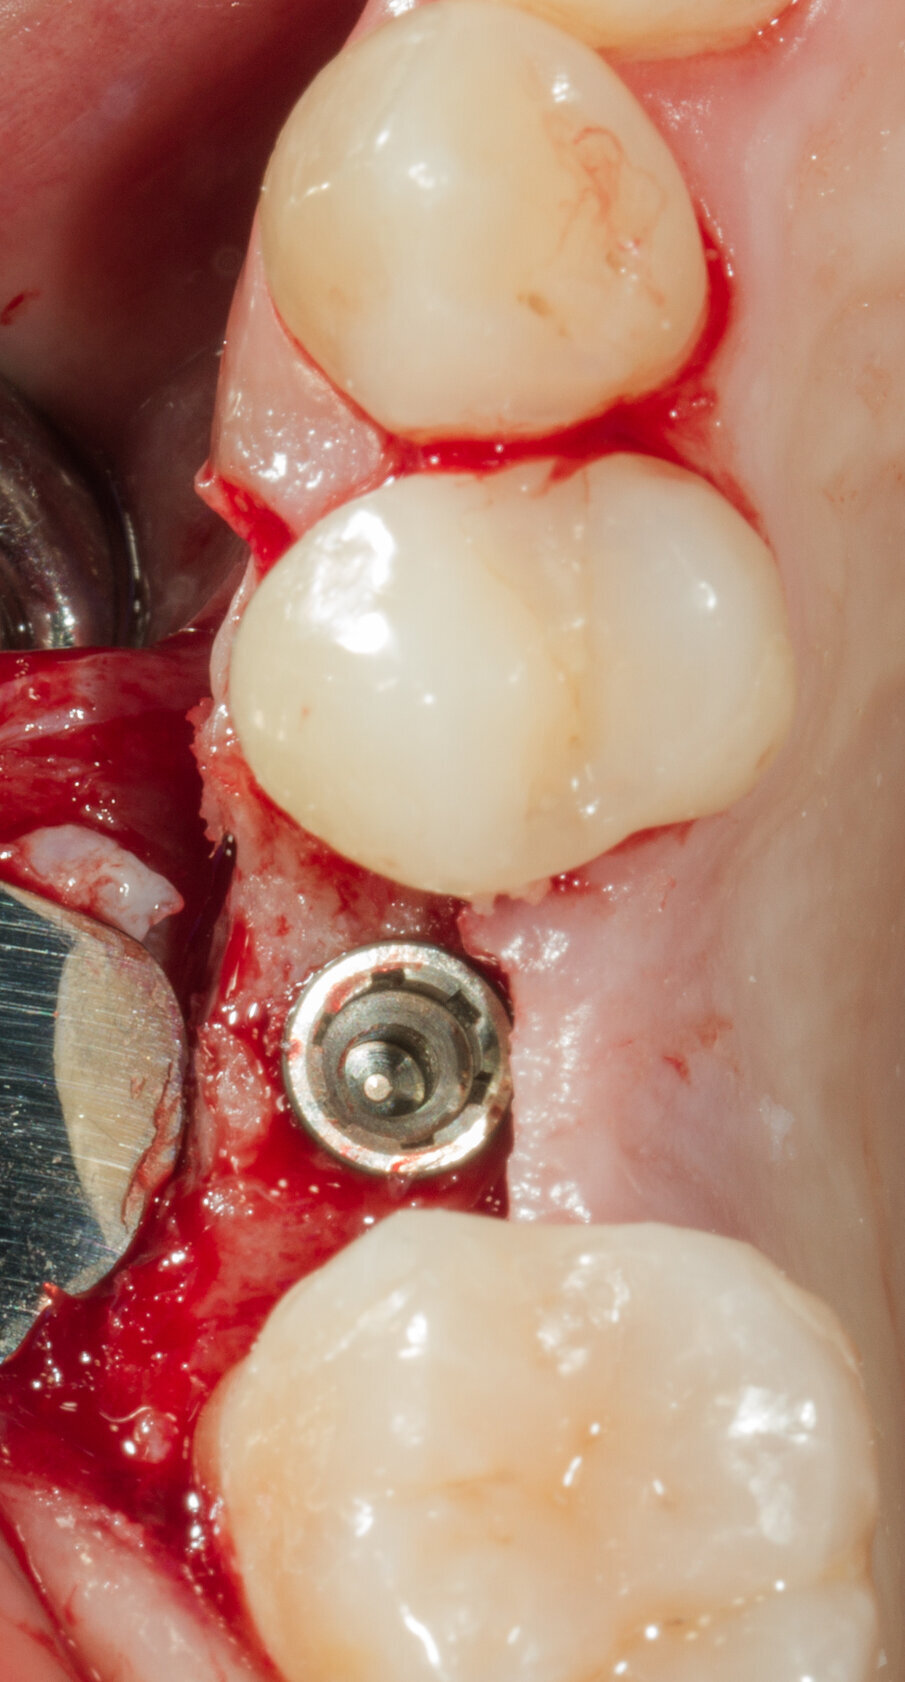

Viene inserito nel centro della cresta neoformata un impianto osteointegrato Neoss Tapered 4.0 x 13 mm con torque di inserimento di 60 Ncm e ISQ 80 (Figg. 22-24). La rigenerazione ossea crestale permette di inserire l’impianto in una posizione protesicamente guidata e con 2 mm di tessuto osseo vestibolare; questa situazione migliora la prevedibilità della riabilitazione implanto-protesica29-33. Dopo 2 mesi di provvisorizzazione si cementa il manufatto protesico definitivo (Figg. 25-28). Il controllo clinico e radiologico a 6 anni (Figg. 29, 30) mostra la stabilità dei tessuti molli e dell’osso perimplantare. Il confronto tra baseline e 6 anni dalla riabilitazione protesica evidenzia la stabilità nel tempo della rigenerazione volumetrica crestale (Fig. 31).

Fig. 22 - Impianto Neoss inserito al centro della cresta ossea.